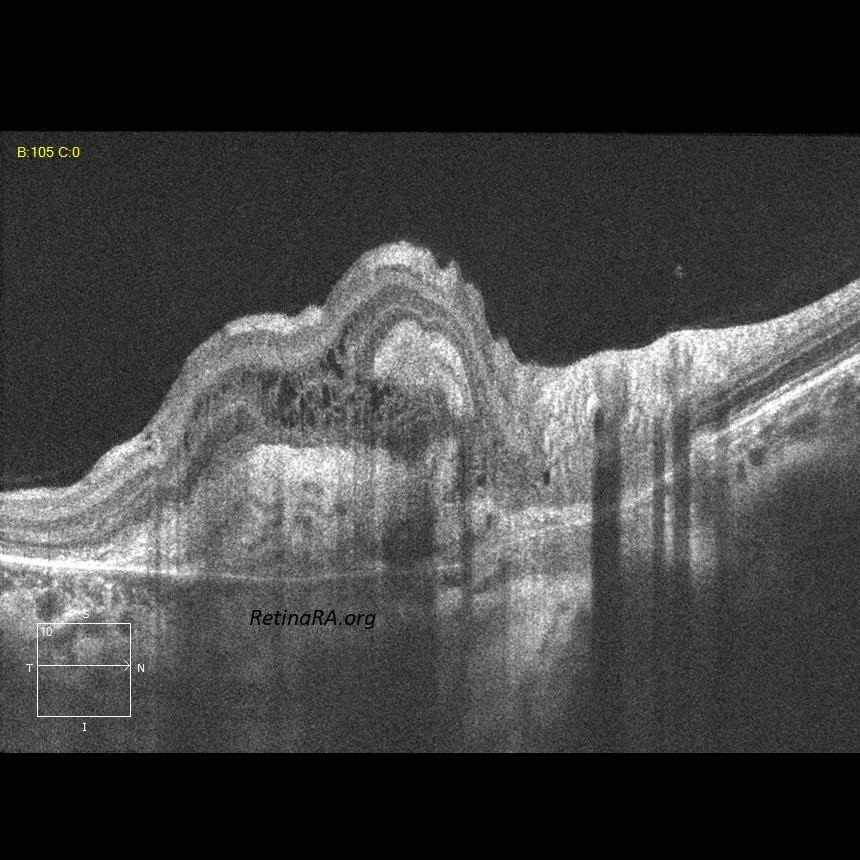

A 26-year-old female patient who complained of decreased visual acuity on the right eye was diagnosed with choroidal neovascular membrane (CNV) secondary to Birdshot retinochoroidopathy. Color photographs show peripapillary CNV in the right eye and bilateral peripapillary birdshot lesions; cream-coloured, irregular or elongated choroidal lesions whose long axis radiates from the optic disc. Atrophic birdshot lesions appear as hypoautofluorescent spots on the autofluorescence image. OCT reveals the CNV as hyperreflective subretinal and intraretinal tissue.